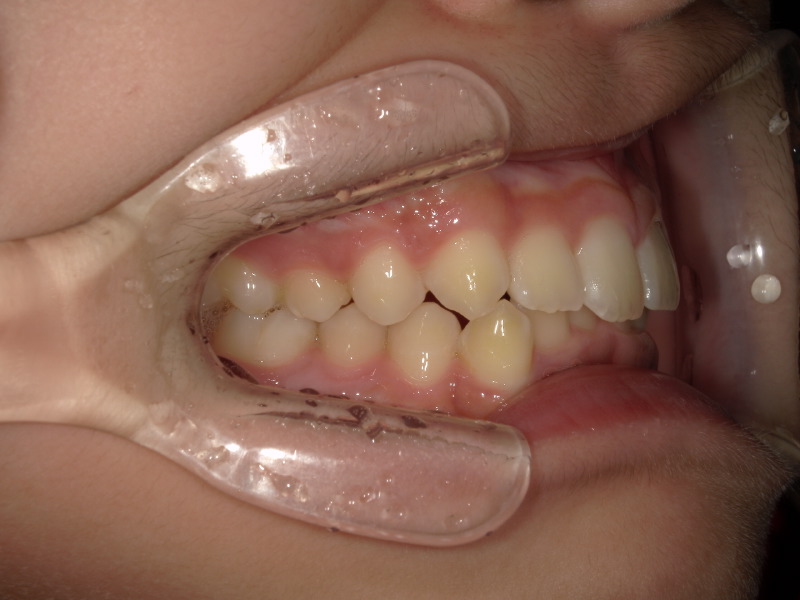

半年後の下の歯の写真です。

がたつきがあったのも綺麗になり、調和の取れた歯並びへ変わってきています!

舌のアクティビティーが少し苦手だったり受験などもあり、3年ほどかかりましたがアクティビティー卒業する頃には綺麗な歯並びになりました!

下の歯もしっかりと見えています。